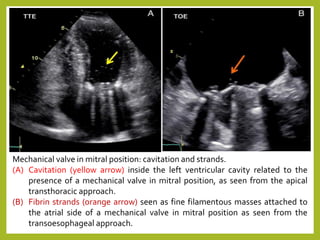

Mechanical valve in mitral position: cavitation and strands.

(A) Cavitation (yellow arrow) inside the left ventricular cavity related to the

presence of a mechanical valve in mitral position, as seen from the apical

transthoracic approach.

(B) Fibrin strands (orange arrow) seen as fine filamentous masses attached to

the atrial side of a mechanical valve in mitral position as seen from the

transoesophageal approach.